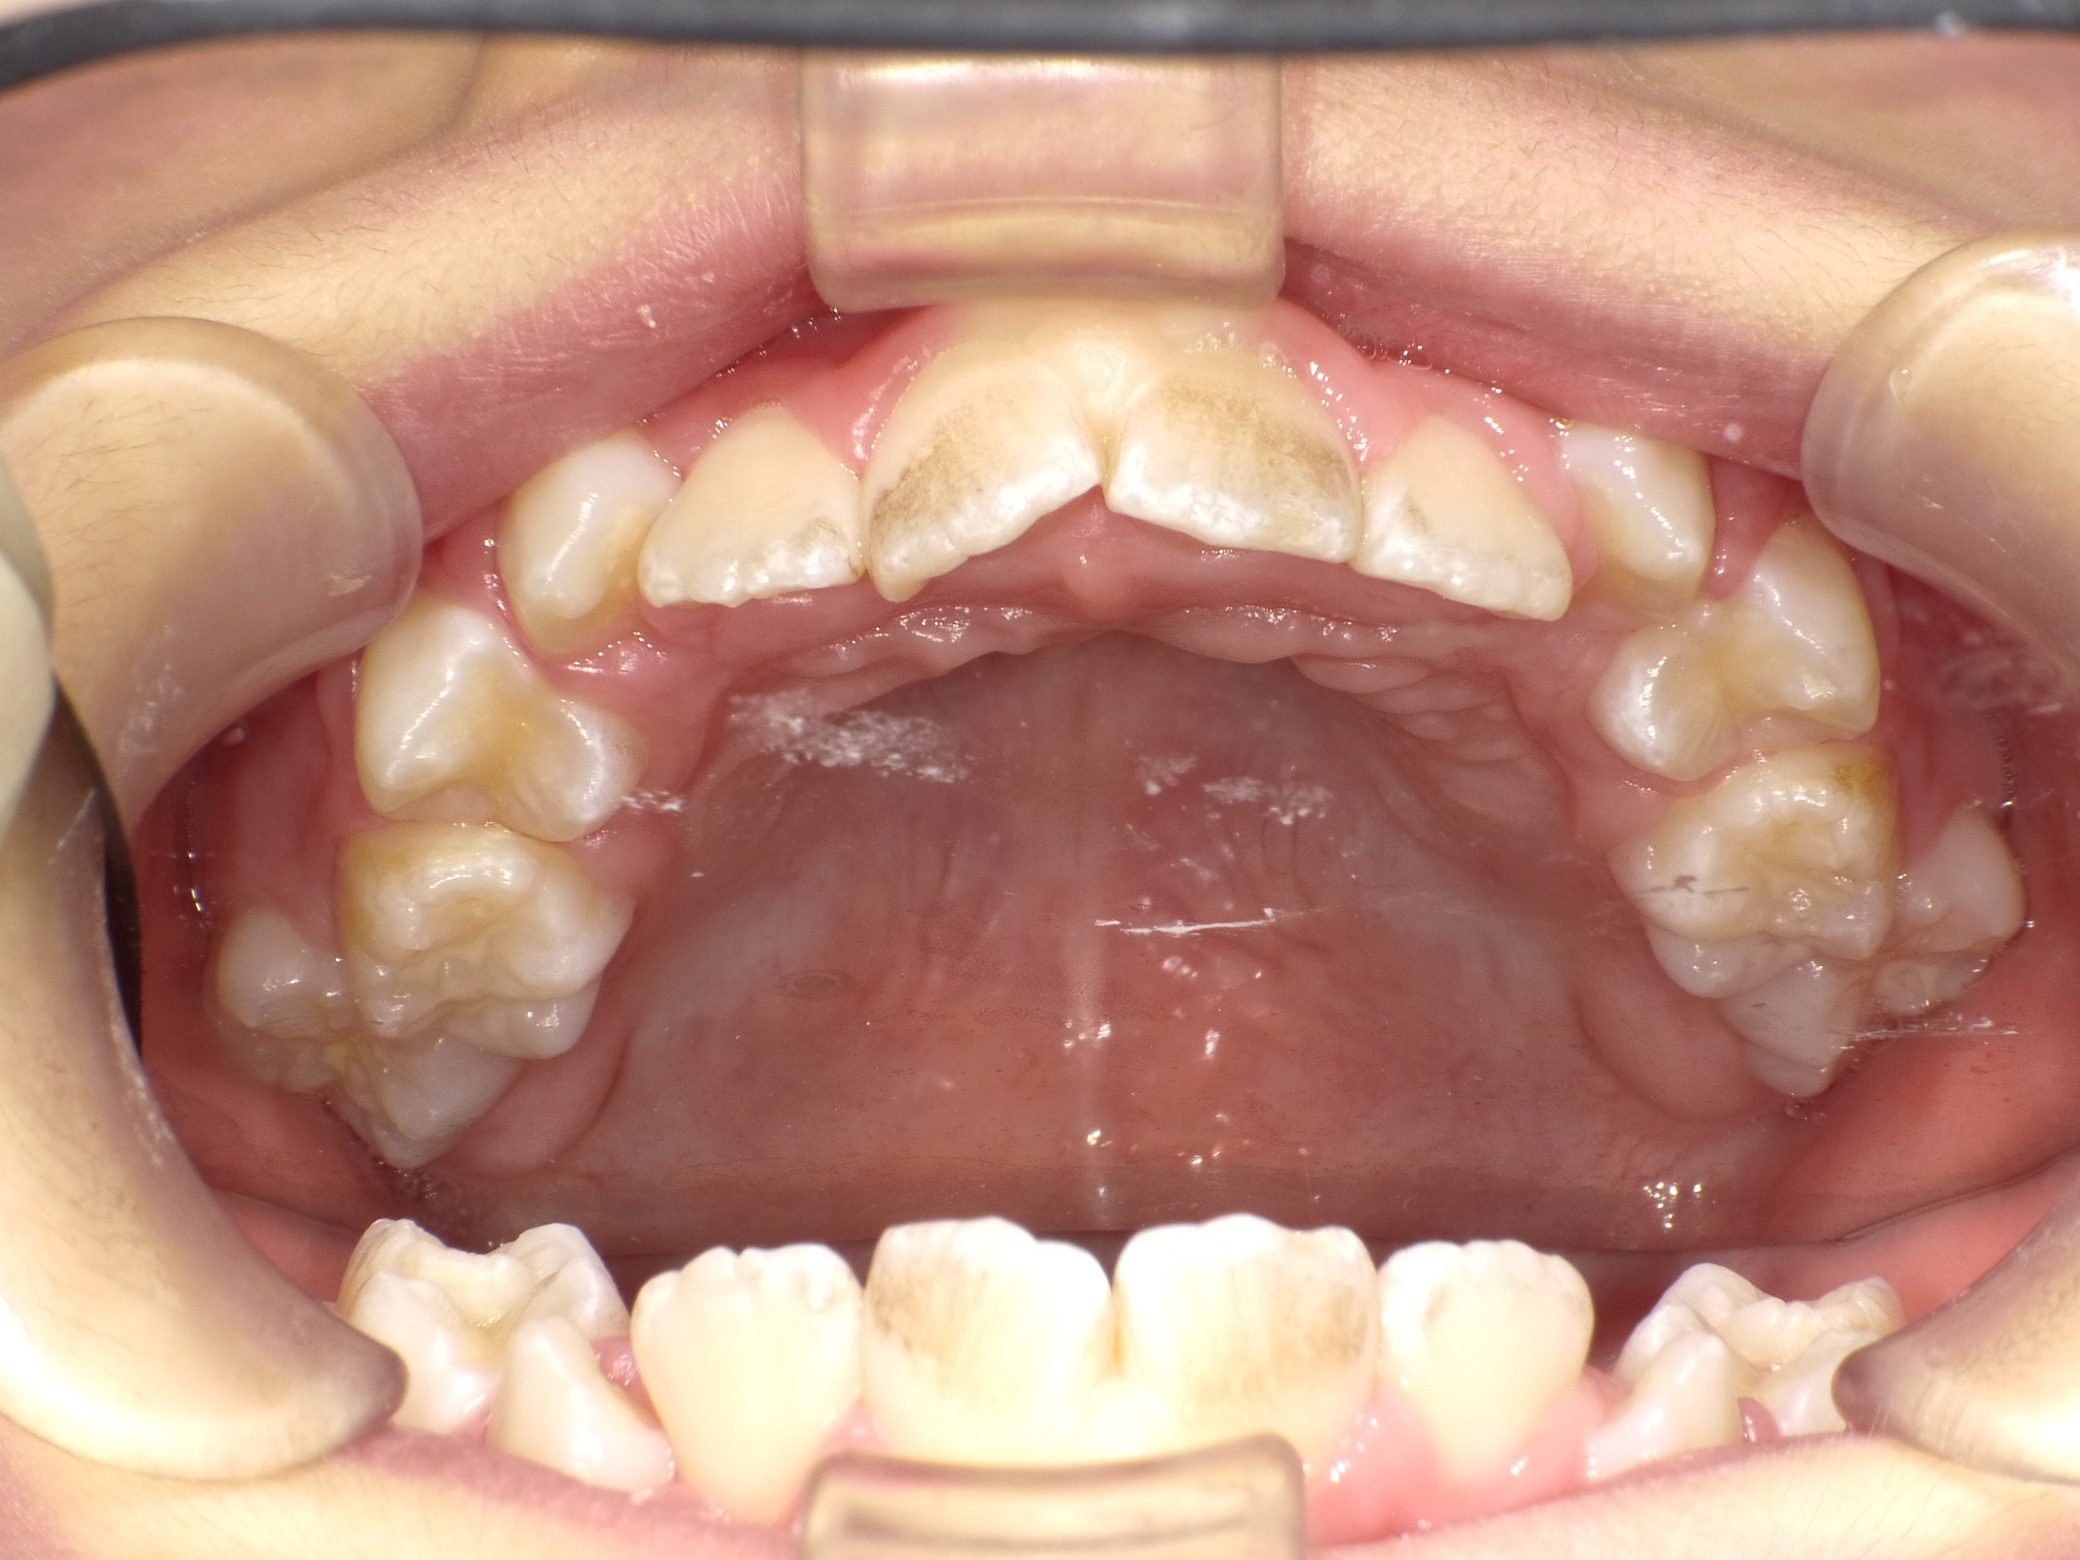

Before

After

【小学生】10歳 マイオブレース矯正 叢生(でこぼこ)と過蓋咬合(深い咬み合わせ)を改善

かなりきちんと取り組んでくれたので、機能矯正装置と MFT(筋機能療法)のみで 改善しています。

機能矯正装置のみで改善するかどうかは もともとの歯並び + 患者さんの装置の使用状況 MFTへの取り組み状況により

変わります。